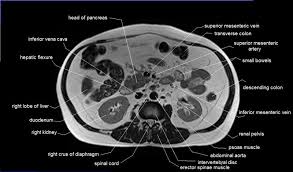

Anatomy pelvis muscles pubococcygeus, puborectalis and iliococcygeus., pelvis nerve, the spinal nerves that arise from vertebral column through the sacrum., pelvic floor musculature laminated anatomy anatomy pelvis muscles; This page provides a photo gallery that presents the anatomy of the abdomen by means of ct (axial, coronal, and sagittal reconstructions). It is strengthened and supported by several joints and ligaments. This is the iliopubic line which outlines the anatomic anterior column this is the ilioischial line which outlines the anatomic posterior column. This mri male pelvis axial cross sectional anatomy tool is absolutely free to use. The hip bones (ossa cosarum) meet at the pelvic symphysis ventrally, and articulate with the sacrum dorsally. Pelvic floor muscles that are located wholly within the pelvis. Almost every movement in the body is the outcome of muscle contraction. There are few important muscles in the abdomen and pelvis. Elevates and retracts the hyoid bone in an action that elongates the floor of the mouth. Discover the muscle anatomy of every muscle group in the human body. The video covers the most. This article reviews the anatomical and functional information of the gastrocnemius muscle, its embryological derivation.

If you want to learn how to read ct scans of the abdomen and pelvis proficiently, this video is an excellent starting point. Learn about anatomy muscles pelvis with free interactive flashcards. Piriformis muscle 1 2 4 3. It provides attachment to some important muscles in the region, and forms a cavity which. Anatomical structures of the abdomen and pelvis are visible as interactive labeled images.

Anatomy of the thorax, heart, abdomen and pelvis the following video will go through normal abdominal anatomy on ct imaging. The pelvis is a basin shaped bony structure formed by the combination of two pelvic bones (hip bones or innominate bones) and the sacrum. Discover the muscle anatomy of every muscle group in the human body. This article reviews the anatomical and functional information of the gastrocnemius muscle, its embryological derivation. Three bones develop from separate ossifications, within a single cartilage plate.

They support the pelvic organs especially during increases in intra abdominal pressure and also aid in urinary and faecal. It is strengthened and supported by several joints and ligaments. Almost every movement in the body is the outcome of muscle contraction. The video covers the most. Anatomy of the thorax, heart, abdomen and pelvis the following video will go through normal abdominal anatomy on ct imaging. This mri male pelvis axial cross sectional anatomy tool is absolutely free to use. Muscles, connected to bones or internal organs and blood vessels, are in charge for movement. Anatomical structures of the abdomen and pelvis are visible as interactive labeled images.